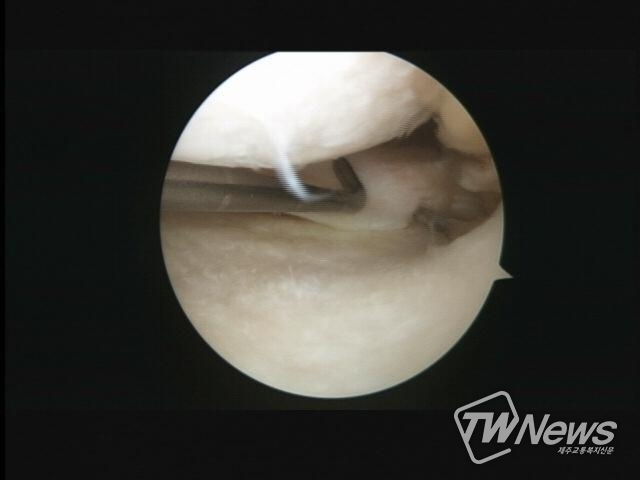

이와 함께 관절내시경을 통한 수술도 가능하다. 4mm 정도의 가느다란 내시경을 손상 부위에 넣어 맨눈으로 환부를 확인하며 진단과 치료를 동시에 할 수 있는 치료로, 관절 내부를 초소형 카메라를 통해 직접 들여다보기 때문에 정확한 관찰이 가능하다. 여기에 기존 절개술보다 절개 범위가 작아 수술 후 빠른 회복도 기대할 수 있다.